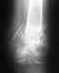

отрывной перелом латерального мыщелка плечевой кости

состоящий из 2х сегментов,смещение примерно 3мм.Суставные поверхности чёткие,ровные,суставные щели не сужены.Структура и форма костей не изменена.Признаков дегенеративныхвоспалительных изменений не выявлено!возраст 25летЭто заключение КТ! подскажите пожалуста кто может.Возможно ли что в этом случае просто накладывается гипс и всё?Очень смушают осколки и цыфра 3мм! Заранее благодарен!